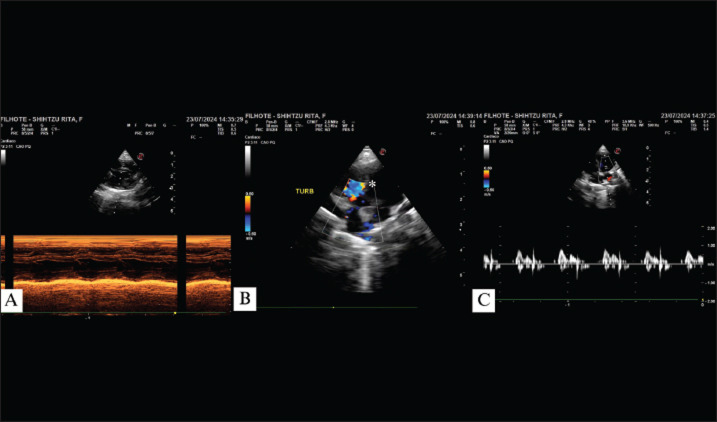

Case description: This article reports a case of PPH in association with a ventricular septal defect (VSD) in a pediatric canine patient. The dog, a female Shih Tzu, aged 2 months, presented with cyanosis, low weight, decreased body condition score (3/9), and underdevelopment in comparison with other puppies of the same litter. At physical examination, all parameters were within the normal range; however, there was a sound at the base of the heart during auscultation, and echocardiographic examination displayed VSD. Due to the dyspnea, thoracic radiography was performed, and the suspicion of PPH was confirmed. Peritoneopericardial hernioplasty surgery was indicated for a 2-month-old patient. During the surgical procedure, it was not necessary to enter the thoracic cavity in order to close the defect, and suture surgery was performed through the abdominal cavity accessed in the subxiphoidal region. Despite the high risks associated with the procedure, no intraoperative or anesthetic complications occurred.